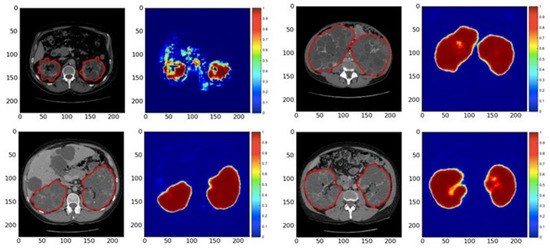

- Sharma, K.; Rupprecht, C.; Caroli, A.; Aparicio, M.C.; Remuzzi, A.; Baust, M.; Navab, N. Automatic Segmentation of Kidneys using Deep Learning for Total Kidney Volume Quantification in Autosomal Dominant Polycystic Kidney Disease. Sci. Rep. 2017, 7, 2049. [Google Scholar] [CrossRef] [PubMed]

- Bevilacqua, V.; Brunetti, A.; Cascarano, G.D.; Palmieri, F.; Guerriero, A.; Moschetta, M. A Deep Learning Approach for the Automatic Detection and Segmentation in Autosomal Dominant Polycystic Kidney Disease Based on Magnetic Resonance Images; SpringerLink: New York, NY, USA, 2018. [Google Scholar]